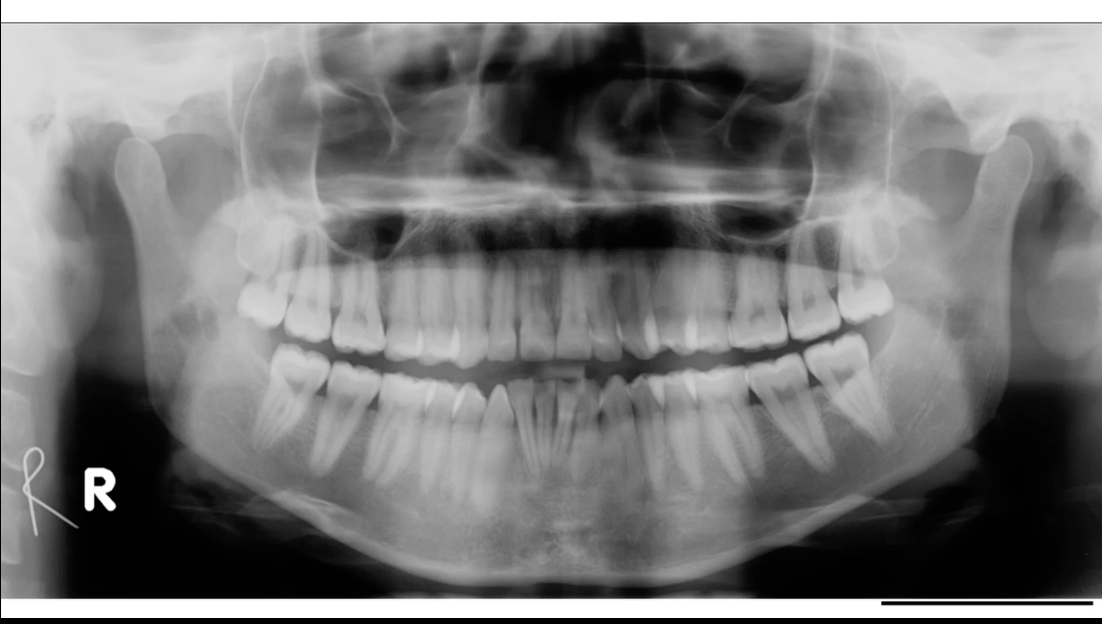

DPT- show full mandible and maxilla, roots, crowns can give good assessment of dentition

useful for patients with a large lesion in the bone as it can show a large area at once

Lower right(mandible) quadrant- molars

Lower right quadrant- two molars each with two roots, and two premolars, crown not as wide as molar and have a single tapering root

for mandibular teeth, apex/ root points upwards and crown points downwards- mandibular teeth are opposite rotation